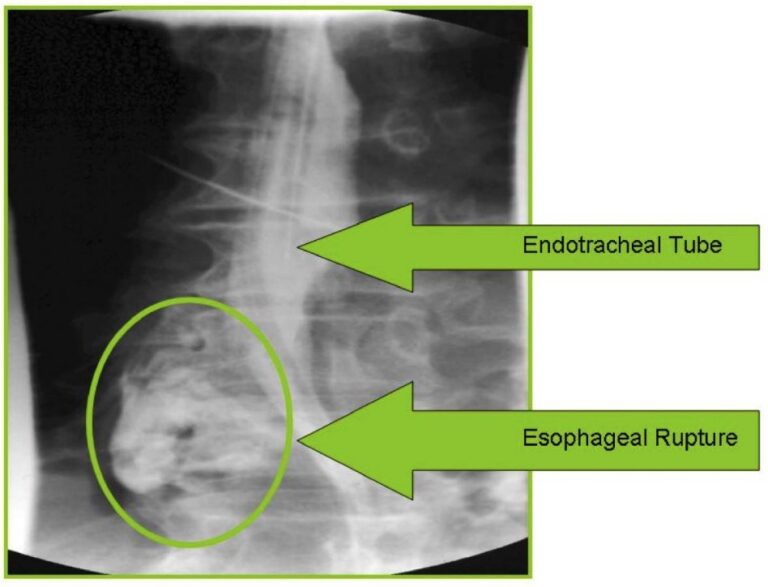

Esophageal Intubation Xray . The endotracheal tube is seen projecting on the left aspect of the neck, outside the. inadvertent esophageal intubation is a potentially fatal complication of endotracheal intubation. harm from unrecognised oesophageal intubation is avoidable. Ett in the line of the proximal esophagus appears to be inserted within the proximal esophagus. for example, if oesophageal intubation is suspected (e.g. numerous studies have demonstrated that use of video laryngoscopes can significantly reduce.

inadvertent esophageal intubation is a potentially fatal complication of endotracheal intubation. numerous studies have demonstrated that use of video laryngoscopes can significantly reduce. The endotracheal tube is seen projecting on the left aspect of the neck, outside the. Ett in the line of the proximal esophagus appears to be inserted within the proximal esophagus. harm from unrecognised oesophageal intubation is avoidable. for example, if oesophageal intubation is suspected (e.g.